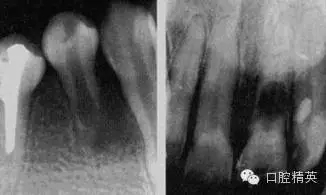

急性化膿性根尖周炎又稱急性牙槽膿腫,是由急性漿液性根尖周炎發(fā)展而來的,也可由慢性根尖周炎急性發(fā)作所致。急性化膿性根尖周炎在其發(fā)展過程中,因其膿液所在部位不同而劃分為根尖膿腫、骨膜下膿腫和黏膜下膿腫三個(gè)階段,主要癥狀為疼痛和腫脹,嚴(yán)重者伴有全身癥狀。

1.根尖膿腫 患牙有自發(fā)性、持續(xù)性、定位性劇烈跳痛,患牙浮起,咬合痛;檢查患牙叩痛、松動(dòng)明顯,根尖部牙齦潮紅,有輕度捫痛。牙髓無活力。

2.骨膜下膿腫 患牙持續(xù)性劇烈跳痛達(dá)最高峰,更覺高起、松動(dòng),觸痛劇烈,相應(yīng)頜面部軟組織腫脹、壓痛,并伴有全身癥狀;檢查患牙為重度叩痛、Ⅲ°松動(dòng),牙齦紅腫,移行溝變平,壓痛明顯,捫診有深部波動(dòng)感,牙髓無活力。

3.黏膜下膿腫 膿液已達(dá)黏膜下,疼痛減輕,全身癥狀緩解;檢查患牙叩痛(+)—(++),松動(dòng)I°,根尖區(qū)黏膜腫脹呈半球形隆起,波動(dòng)感明顯,牙髓無活力。

1.診斷 左下6急性化膿性根尖周炎(骨膜下膿腫)。

診斷依據(jù):患牙有深齲,松動(dòng)Ⅲ°,叩痛(+++),根尖部牙齦紅腫、捫痛、波動(dòng)感等牙槽膿腫的典型癥狀。同時(shí)伴有左側(cè)面頰部水腫,體溫38℃等全身癥狀。